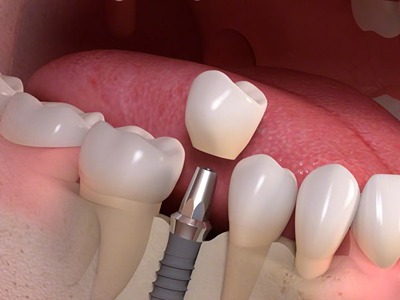

You can rely on us for dependable, comfortable, and expert dental care. With advanced technology, experienced specialists, and personalized treatment plans, we ensure every patient receives trusted, effective solutions for long-term oral health and confident smiles.

Dr Nitesh Rai, specializes in replacement of teeth with complete dentures, removable partial dentures, fixed partial dentures and Implants.